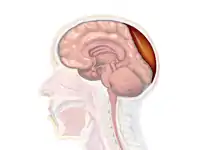

Epidural hematoma commonly results from a blow to the side (temporal bone) of the head. The pterion region, which overlies the middle meningeal artery, is relatively weak and prone to injury.[11] Only 20 to 30% of epidural hematomas occur outside the region of the temporal bone.[12] The brain may be injured by prominences on the inside of the skull as it scrapes past them. Epidural hematoma is usually found on the same side of the brain which was impacted by the blow, but on very rare occasions it can be due to a contrecoup injury.[13]

Epidural hematomas usually appear convex in shape because their expansion stops at the skull's sutures, where the dura mater is tightly attached to the skull. Thus, they expand inward toward the brain rather than along the inside of the skull, as occurs in subdural hematomas. Most people also have a skull fracture.[3]